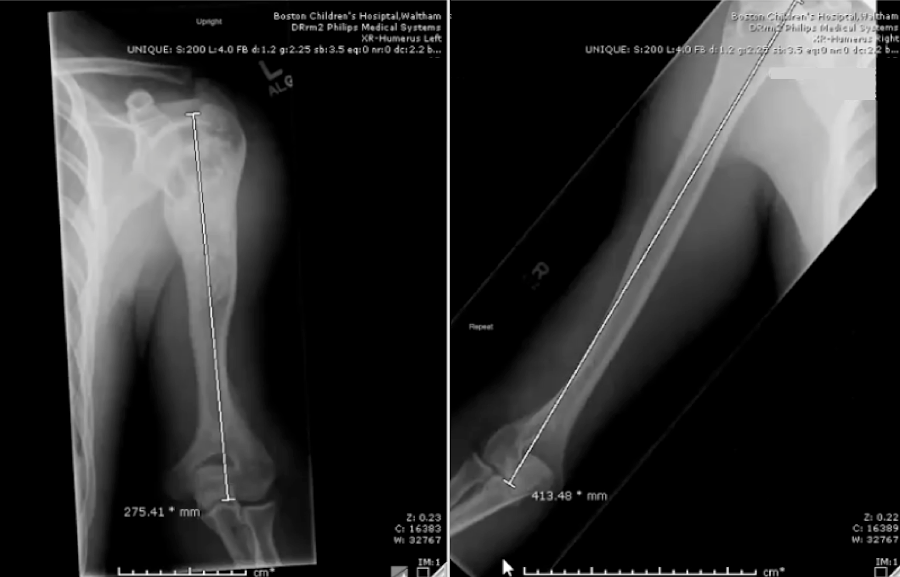

Complex case: Humeral lengthening using a lower extremity device

At left: A look at a young man’s arm that had stopped growing. At right: The arm after two years of limb-lengthening treatment.

Treatment to remove a bone cyst in this patient’s upper left arm when he was 8 years old stopped further growth in that arm. By the time he was 18, his right arm had grown 138 millimeters longer than his left. Over the course of two summers, surgeons in the Limb Lengthening and Reconstruction Program lengthened his left arm using the PRECICE Nail internal lengthening device.